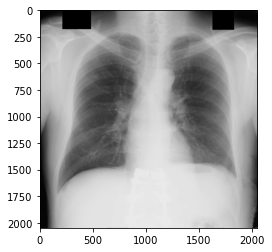

日本放射線技術学会 画像部会がDICOM形式の胸部腫瘤陰影像の標準ディジタル画像データベースを無償で提供してくれていますので、今回はこのデータセットをありがたく利用させていただきます。

画像の表示

import numpy as np import matplotlib.pyplot as plt from pydicom import * d = dcmread('./Nodule154images/JPCLN001.dcm') arr = d.pixel_array plt.imshow(arr, cmap="gray") plt.show()

このようにほぼ真っ白になってしまいました(データは先ほど画像の表示をしたJPCLN001.dcmです)。